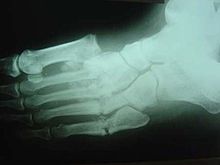

Oblique view X-ray in a 45-year-old male diabetic revealed a divergent, Lisfranc dislocation of the first metatarsal with associated lesser metatarsal fractures.

The same 45-year-old man with diabetes mellitus presented with a diffusely swollen, warm and non-tender left foot due to Charcot arthropathy. There are no changes to the skin itself.

The clinical presentation varies depending on the stage of the disease from mild swelling to severe swelling and moderate deformity. Inflammation, erythema, pain and increased skin temperature (3–7 degrees Celsius) around the joint may be noticeable on examination. X-rays may reveal bone resorption and degenerative changes in the joint. These findings in the presence of intact skin and loss of protective sensation are pathognomonic of acute Charcot arthropathy.